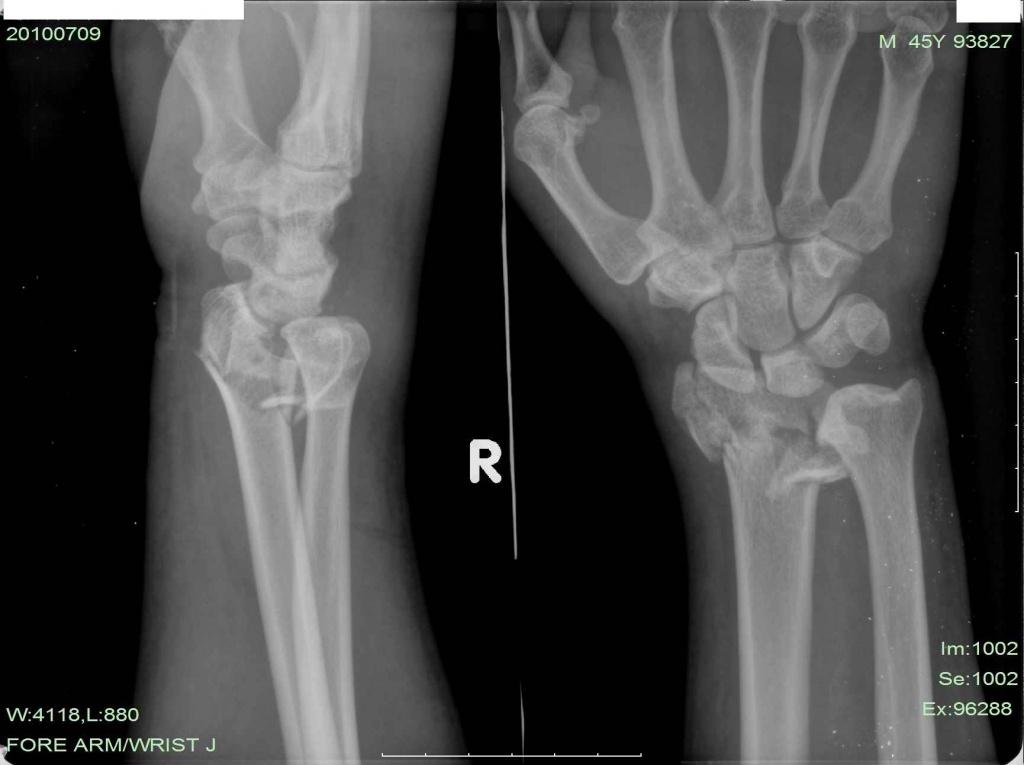

患者男性,45岁,外伤后6天,拟明天行开放复位内固定术。请战友指导手术方案及细节!

x片提示:右桡骨远端严重粉碎性骨折伴下尺桡关节脱位。建议:1.手法复位可能达不到想要的目的,关节面恢复不完整,创伤性关节炎不可避免。病员正是壮年,若是老年人,她对关节活动要求不高的话,也可以,(沟通清楚后)我们遇到很多老年患者,叫做手术,坚决不做,其要求不高。2.对于这个患者,建议手术治疗(手术目的:尽量恢复关节面的完整,恢复关节间隙),治疗方案有三:a掌背侧切开解剖复位,必要时植骨,细钢针固定,恢复关节面,缝合,外固定支架固定。 b,掌背侧切开解剖复位,必要时植骨,细钢针固定,恢复关节面,长的重建钢板自桡骨到第二掌骨固定。c术中看如果远端能曾受螺钉的话,也可以考虑“T”行钢板固定。